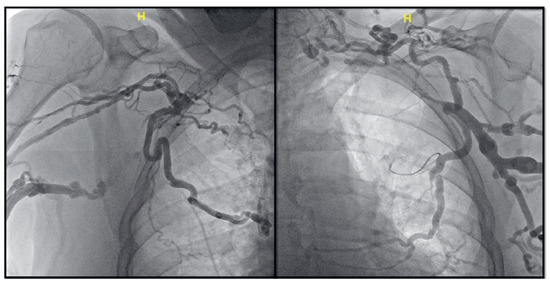

Leadless Pacemaker Placement to Overcome Bilateral Subclavian Vein Occlusion